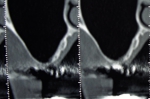

ガイド使用フラップレス骨移植インプラント同時症例

通常これほど骨が薄い場合は上の症例の様な大きな骨の移植が必要となりますが、シュミレーションソフトを使い審査したところギリギリでインプラント埋入と同時に骨の移植を行えると判断。

またシュミレーションを基に作成したインプラント手術ガイドを使用したので歯茎を切らないフラップレスで手術を行うことができました。

フラップレス手術はよくありますが実際は精度が悪くなり術後の歯茎の退縮も起こりやすいので状態が良くないと行わないですが、痛みも少なく患者さんに優しい方法です。

また骨の移植もインプラント埋入の為に開けた穴から空洞内の粘膜を剥がしスペースに移植する方法でこちらも難度が高く半数以上の症例で失敗している(少しの失敗では一部インプラントと結合するので失敗の及ぼす影響はわかりにくいです)という統計データも存在しますが、こちらも術後の痛みも少なく治療期間も大きな移植と比較して6か月程度短縮することができます。

当院では術後にCT撮影を行い結果をごまかさずに患者さんと一緒に確認しています。